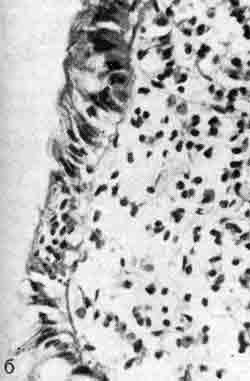

б — деталь предыдущего рисунка. Альтеративные изменения энтероцитов (X 600);

В тонкой кишке выявляется катаральное воспаление с дистрофическими изменениями энтероцитов. Они возникают преимущественно на вершинах кишечных ворсинок. Высота эпителия нормальная. Исчерченная каемка их большей частью сохранена, содержание щелочной фосфатазы здесь не меняется.

Изредка она бывает разрушена, однако обычно в пределах всего лишь 2 — 3 клеток. Число фигур митозов в клетках эпителия слизистой оболочки увеличено. Сколько-нибудь выраженной инфильтрации эпителиального слоя лимфоцитами и плазмоцитами в острой стадии болезни не описывается.

В дальнейшем нередко происходит отторжение части энтероцитов и даже их пластов, особенно на вершинах кишечных ворсинок.

В собственном слое слизистой оболочки наблюдается полнокровие, иногда можно видеть мелкие кровоизлияния. Постоянно обнаруживаются очаговые инфильтраты, состоящие из лимфоцитов, гистиоцитов и плазмоцитов, а также нейтрофильных и эозинофильных лейкоцитов.